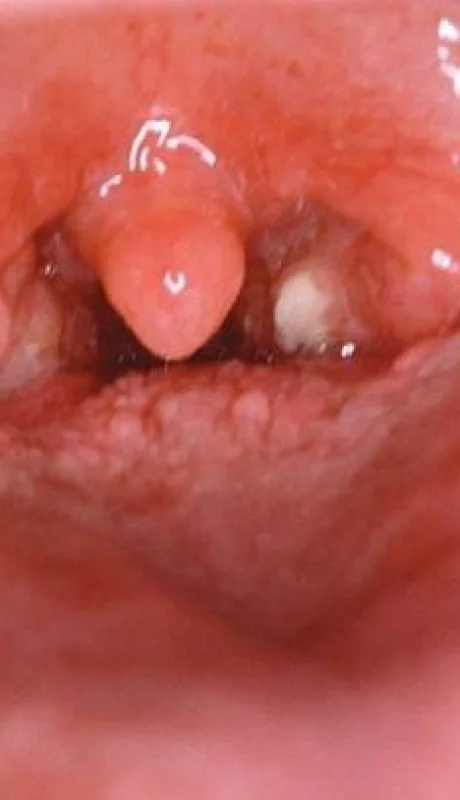

Streptococcus pyogenes: no hay alerta en Mendoza